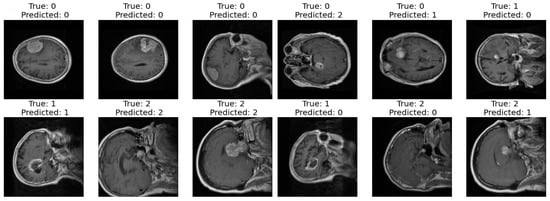

3.1. Proposed Model Generalization